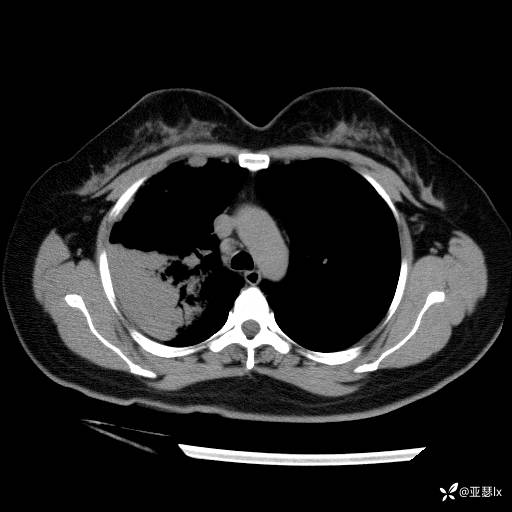

治疗后复查影像学(2023.04.07)

患者体温有所改善,但影像学未见明显变化,后续行肺穿刺活检检查。

总结与讨论

肺实变究竟为何病因:非典型病原体?机化性肺炎?还是其他非感染性因素? @丁香园病例库